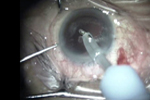

[组图]皮质膨胀乳化的白内障PHACO         ★★★

皮质膨胀乳化的白内障PHACO

手术者-温州医学院眼视光医院 赵云娥主任

部分视频画面